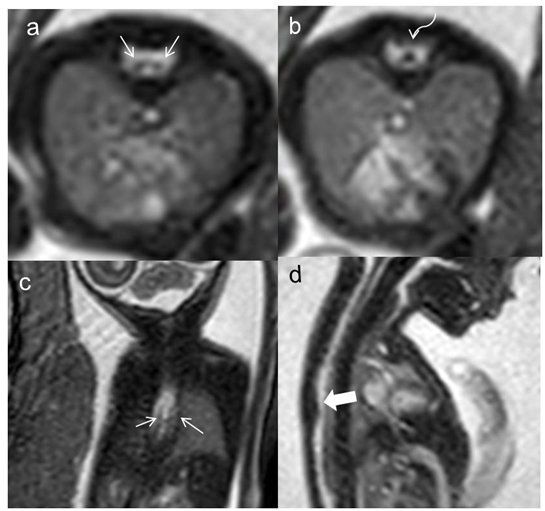

Figure 2 Fetal MRI of the spine in transverse view: coronal (A), axial (B,C) and (D) sagittal sections showing bony spur (thick arrow) separating two hemi cords (thin arrows). g, Hemi cords fused into one cord lower (curved arrow) seen below the region of interest.